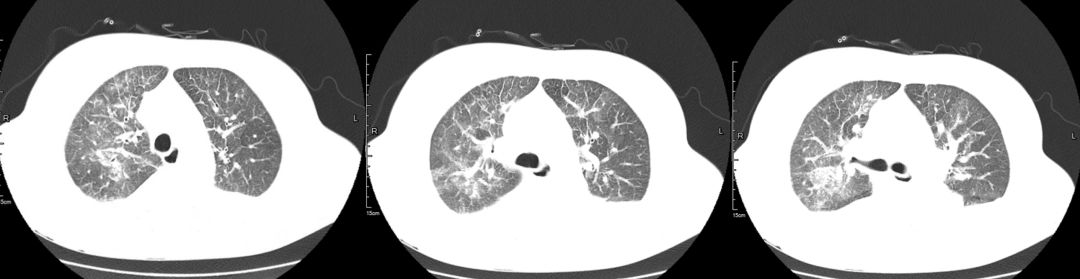

治疗前(2019-03-05)

胸部CT:两肺多发斑片状渗出影,部分实变,两侧胸腔积液,双下肺膨胀不全,两肺门增大,纵隔内多发淋巴结。

3、辅助检查。胸部CT:双肺多发斑片状渗出性,部分实变,双侧胸腔积液。心超:左心增大伴中度二尖瓣关闭不全、主动脉瓣退行性变伴中度关闭不全、肺动脉高压伴轻中度三尖瓣关闭不全、房间隔膨出瘤(未破裂),EF 60% 正常。

该病例中患者影像学提示双肺多发弥漫性渗出影,没有及时鉴别诊断,笼统诊断为肺部感染性疾病,该影像不是肺部病原菌感染特有的表现,它不是感染的代名词。

肿瘤细胞浸润间质所致,咳嗽、咳大量粘液性泡沫性痰,病理可以明确鉴别。该病例中影像学表现密度相对均匀,与大叶性肺炎相比密度稍低,应用加强利尿3天后肺内磨玻璃影迅速吸收,变化快,肺部感染一般需2周甚至更长时间才能吸收,从影像特点及治疗后的反应上来讲均不支持肺炎。